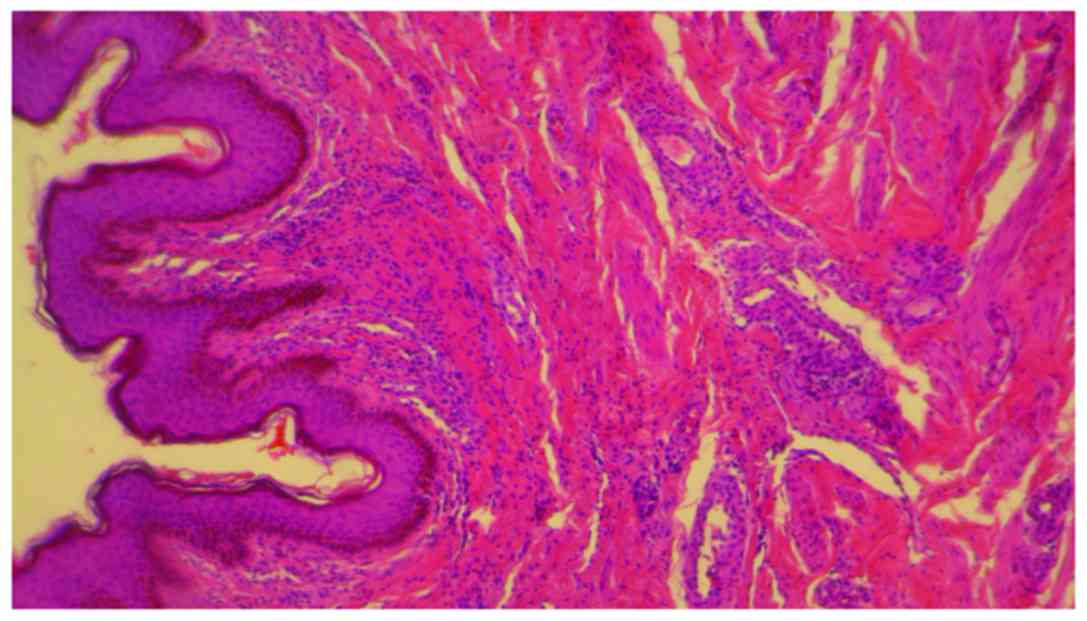

erlotinib, but unfortunately, it was not possible. Skin biopsy was

performed. The histopathology revealed a dense perivascular

neutrophilic infiltration, fibrinoid necrosis of the vessel walls,

leukocytoclastic and red blood cell extravasation, confirming the

diagnosis of cutaneous leukocytoclastic vasculitis (Figs. 3 and 4). The appearance of cutaneous vasculitis